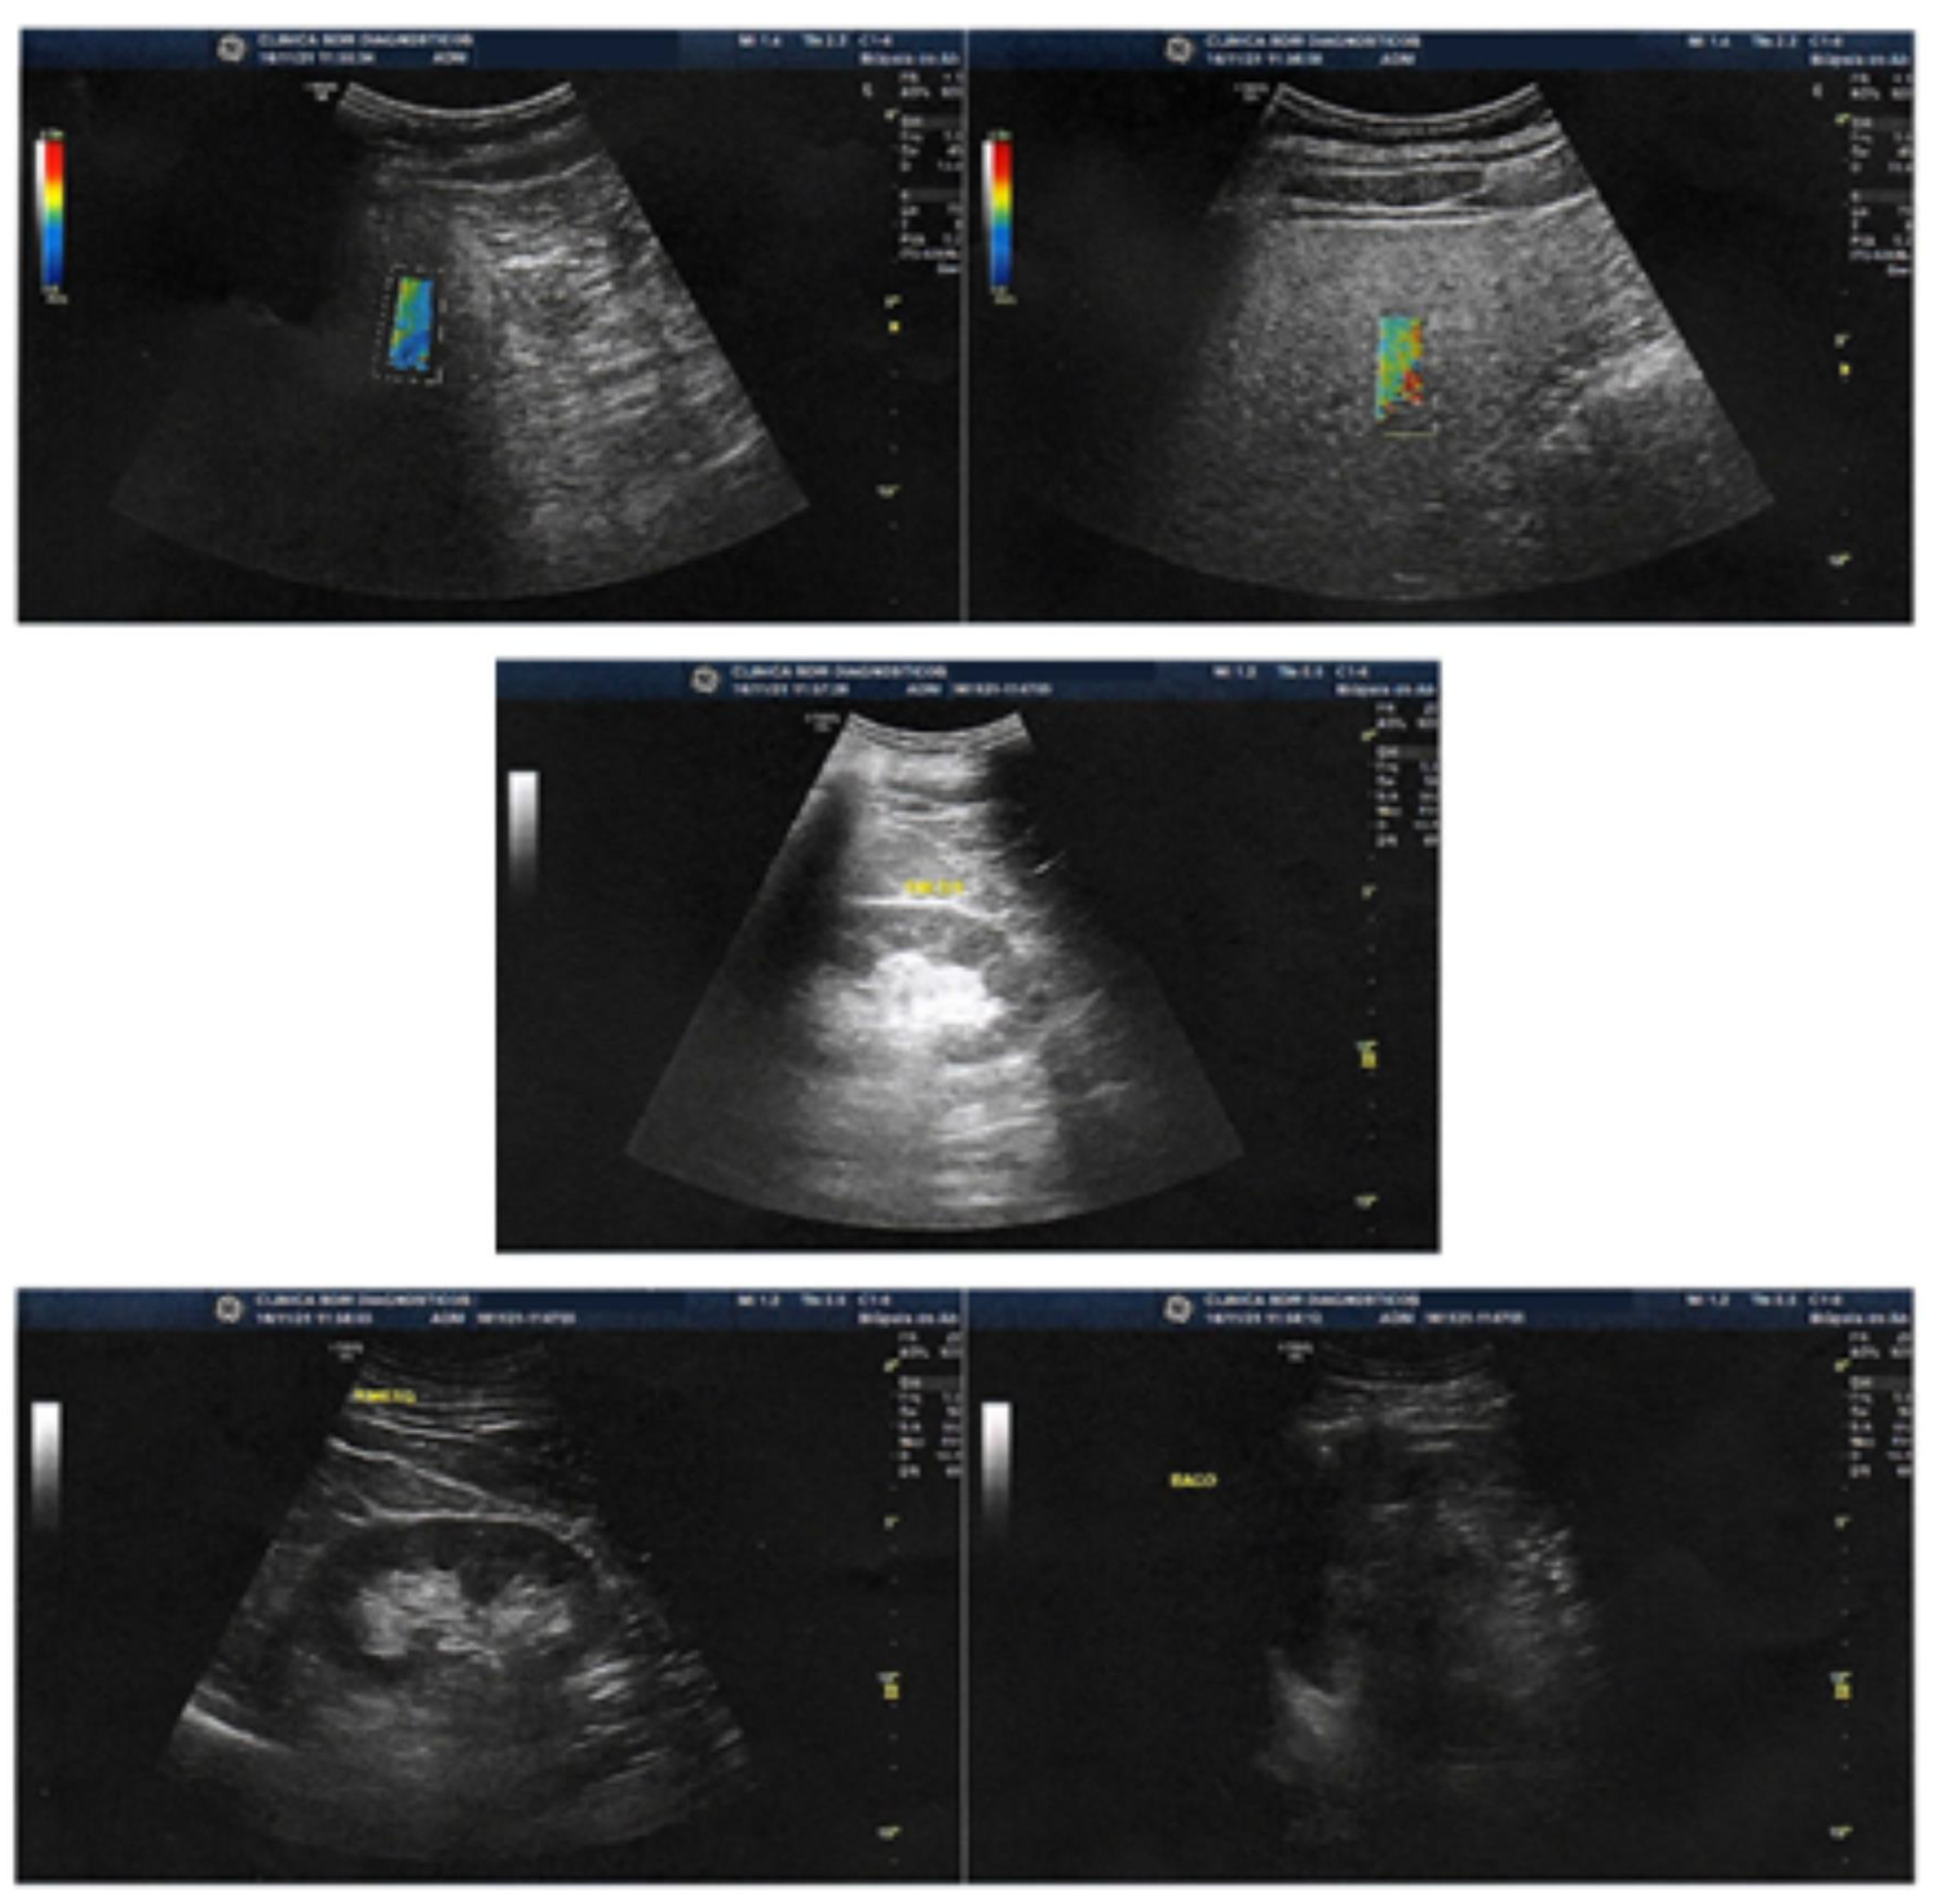

The liver exhibited normal topography, shape, dimensions, contours, and surface. A homogeneous echotexture of the liver parenchyma was observed, showing signs of mild fatty infiltration but without any focal lesions. Elastography was conducted using the shear wave method [19,24] with the Logiq S8 device developed by GE Healthcare (Chalfont St. Giles, Buckinghamshire, UK).

The elastography results demonstrated a mean stiffness measurement of 5.70 kPa, which corresponds to non-significant fibrosis (F0–F1) on the METAVIR scale [22]. The stiffness range fell between 2.5 and 7 kPa, indicating minimal fibrotic changes within the liver (Figure 3 and Figure 4, Table 3). The IQR/median was 15.4%.

The utilization of the shear wave elastography technique with the Logiq S8 device allowed for accurate and quantitative assessment of liver stiffness, providing valuable insights into the patient’s liver health status. The accompanying figures (Figure 3 and Figure 4) and table (Table 3) visually depict the elastography results, reinforcing the observed improvements in liver structure and fibrosis severity.

Figure 3. Images show liver with normal topography, shape, dimensions, contours and surface. Homogeneous liver parenchyma echotexture, with signs of mild fatty infiltration, without focal lesions. Elastography with the shear wave method (Logiq S8) showing mean stiffness (Kpa) of 5.70 corresponding to non-significant fibrosis (FO-F1) on the METAVIR scale.